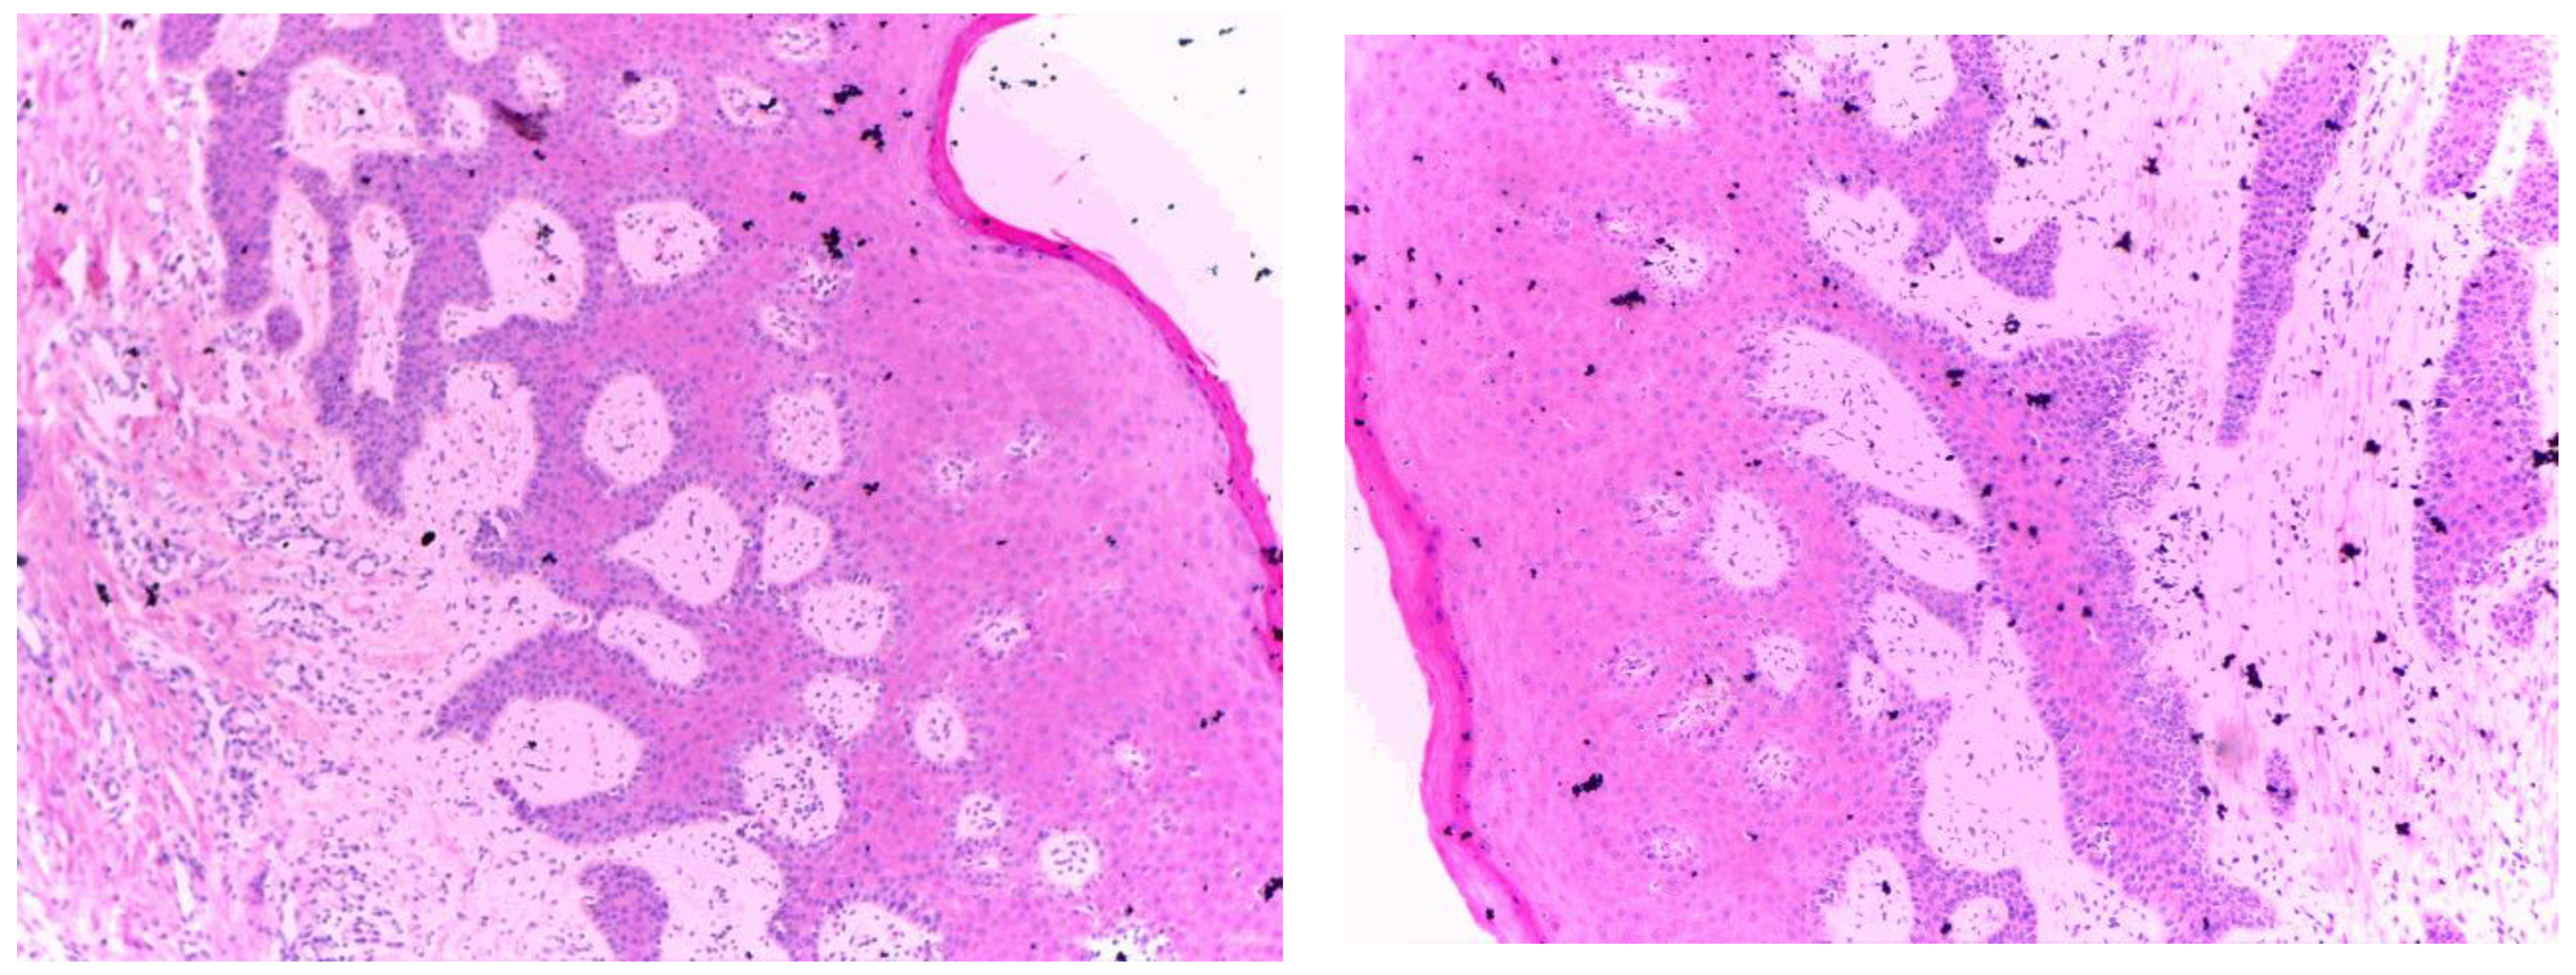

3.2.3. Histopathological Results